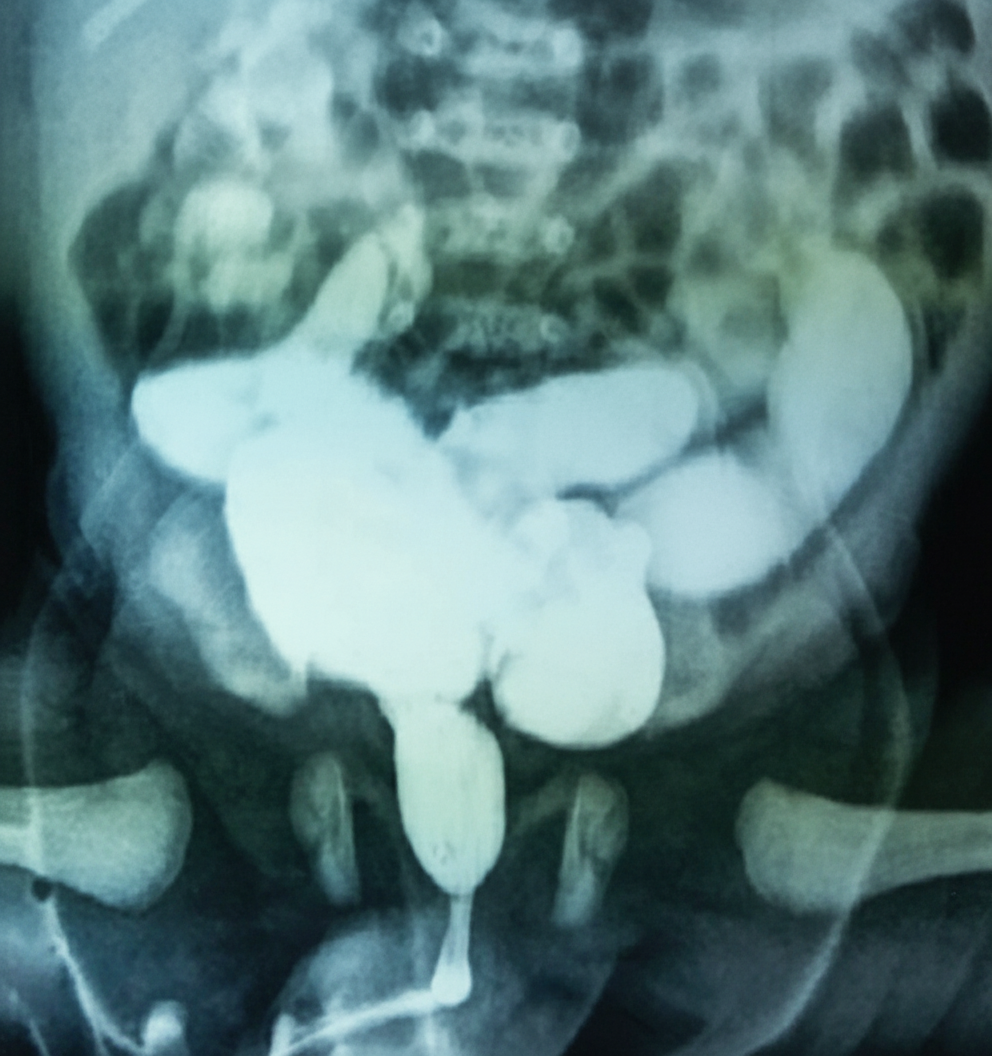

Physical examination of a neonate reveals a distended bladder and palpable kidneys. The infant produces a weak urinary stream. A voiding cystourethrogram is shown. He appears to be otherwise normal. Which of the following is the most likely diagnosis?

Explanation: ***Posterior urethral valve*** - **Voiding cystourethrogram** shows **dilated posterior urethra** with **keyhole sign** and **trabeculated bladder**, pathognomonic for posterior urethral valves in male neonates. - Clinical presentation of **distended bladder**, **palpable kidneys**, and **weak urinary stream** is classic for **infravesical obstruction** caused by posterior urethral valves. *Ureteropelvic junction obstruction* - Would cause **hydronephrosis** but **normal bladder** appearance on imaging, not the distended bladder seen here. - Typically presents with **flank pain** or **palpable flank mass**, not bladder distension or weak urinary stream. *Prune belly syndrome* - Characterized by **absent abdominal wall musculature**, **cryptorchidism**, and **urinary tract abnormalities** - not just isolated urinary symptoms. - VCUG would show **tortuous, dilated ureters** and **large bladder**, but without the **keyhole sign** of posterior urethra dilation. *Duplication of the collecting system* - Usually **asymptomatic** in neonates or presents with **recurrent UTIs**, not bladder distension or weak stream. - VCUG would demonstrate **duplicated collecting systems** with possible **vesicoureteral reflux**, not posterior urethral dilation.